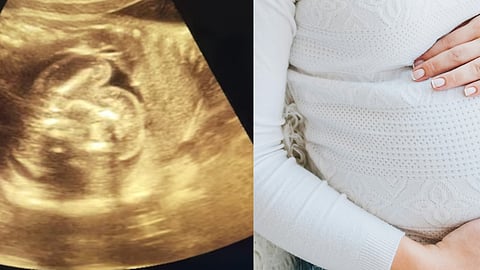

மகாராஷ்டிராவில் கர்ப்பிணியின் வயிற்றுக்குள் இருக்கும் கருவில் மற்றொரு கரு இருப்பது கண்டறியப்பட்டுள்ளது.

மகாராஷ்டிரா மாநிலம் புல்தானா பகுதியில் உள்ள அரசு மருத்துவமனையில், கடந்த இரண்டு நாட்களுக்கு முன்பு, 32 வயதான கர்ப்பிணிக்கு சோனோகிராபி செய்து பார்க்கப்பட்டுள்ளது.

அப்போது ஸ்கேனில், கர்ப்பிணியின் கருவில் இருந்த கருவிற்குள், மற்றொரு கரு இருப்பது கண்டறியப்பட்டுள்ளது. இதனால், ஆச்சரியமடைந்த மருத்துவர், இதை மீண்டுமொருமுறை உறுதிசெய்ய உடனடியாக வேறு மருத்துவர்களிடத்தில் ஸ்கேனை காண்பித்துள்ளார்.

இதுகுறித்து கர்ப்பிணிக்கு சிகிச்சையளித்த மகப்பேறு மருத்துவர் பிரசாத் அகர்வால், கூறுகையில், “இதை பார்த்ததும் ஆரம்பத்தில் நான் ஆச்சரியமடைந்தேன். பிறகு, மீண்டும் அந்த ஸ்கேனை உற்று நோக்கினேன். அப்போதுதான், கருவில் உள்ள இன்னொரு கரு வளர்ச்சியடையாமல் இருக்கிறது என்று தெரிந்தது. பிறகு இரண்டு மருத்துவர்களிடத்தில் இதை காண்பித்து உறுதி செய்துகொண்டேன்” என்றுள்ளார்.

இதுகுறித்து தெரிவித்துள்ள மருத்துவர்கள், இது மிகவும் அரிதானது எனவும், உலகிலேயே இதுவரை 200 சம்பங்கள்தான் இதுபோன்று பதிவாகியுள்ளதாகவும், அதில், இந்தியாவில் 15 - 20 வழக்குகள் மட்டுமே பதிவாகியுள்ளது என்றும் தெரிவித்துள்ளனர்.

9 ஆவது மாதம் வரை அந்தப் பெண்ணின், முந்தைய ஸ்கேன்களில் இதுகுறித்து எதுவும் தென்படாத நிலையில், இந்த ஸ்கேனில்தான் இவ்விஷயம் கண்டறியப்பட்டுள்ளது..

தொடர்ந்து கருவுக்குள் இருக்கும் கருவை என்ன செய்வது என்பது குறித்து தாயிடம் தகுந்த ஆலோசனை செய்த பின்னர் முடிவெடுக்கப்படும் என்று மருத்துவர்கள் தெரிவித்துள்ளனர். இந்த சம்பவம் மருத்துவ உலகில் பேசுபொருளாக மாறியுள்ளது.